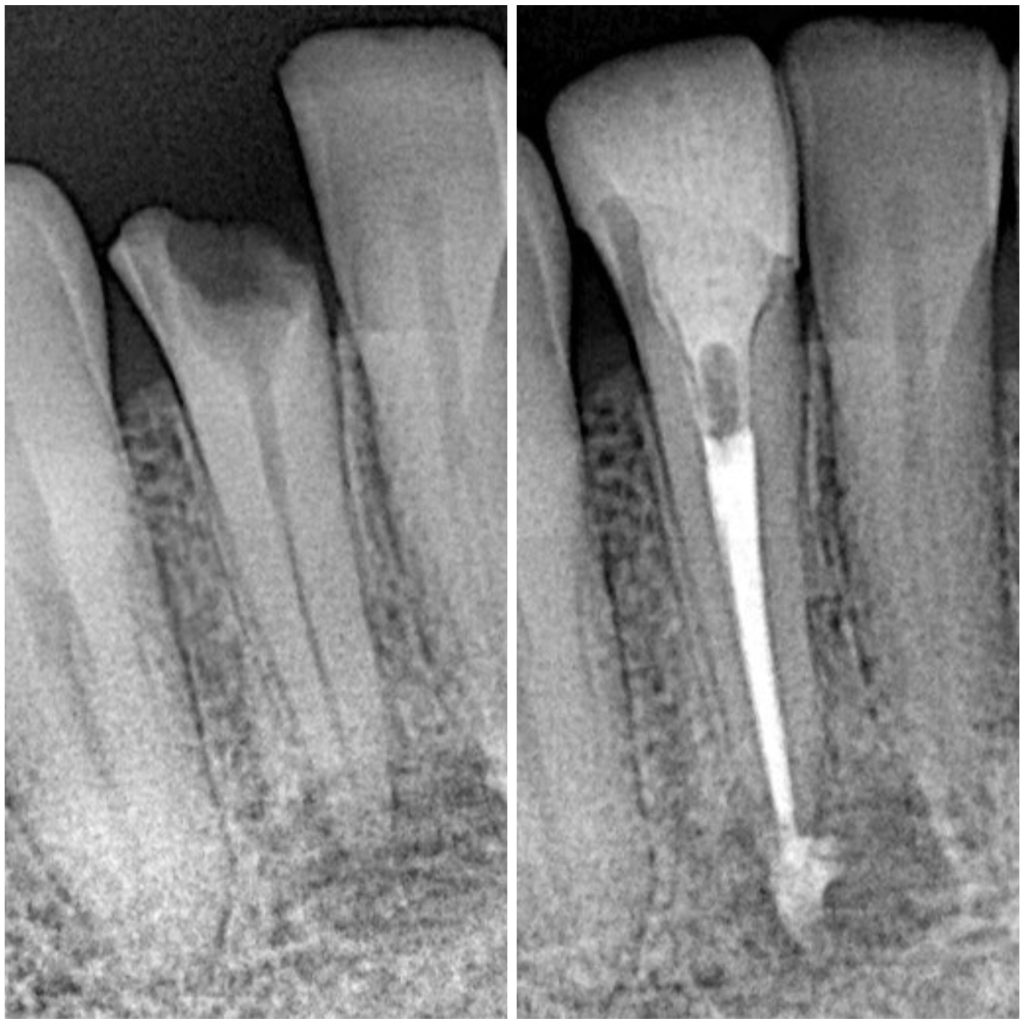

Fractured Lower lateral incisor was necrotic and had periapical lesion as seen in X-ray

-Endodontic treatment with Bioceramic sealer and single cone